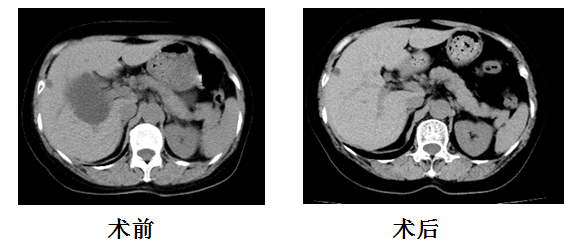

临床真实案例:

张大娘(化名),因右上腹疼痛于我院门诊体检发现肝脏多发囊肿(右叶囊肿最大截面76.54mm*70.25mm)就诊于我科,我科在排除禁忌症后,予以行肝囊肿穿刺抽液+硬化术,术后半年复查囊肿完全消失。